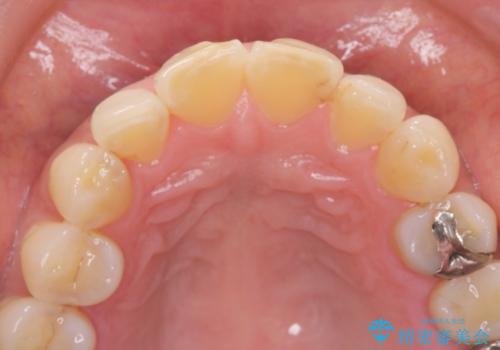

- 前歯の形が気に入らなく、粗造な感じがして色も気に入らないとの事で来院。

適合の良い被せ物が入りました。

樹脂の素材とは違い、セラミックやジルコニアの素材の被せ物は劣化をしません。また、虫歯の再発リスクも低くなります。